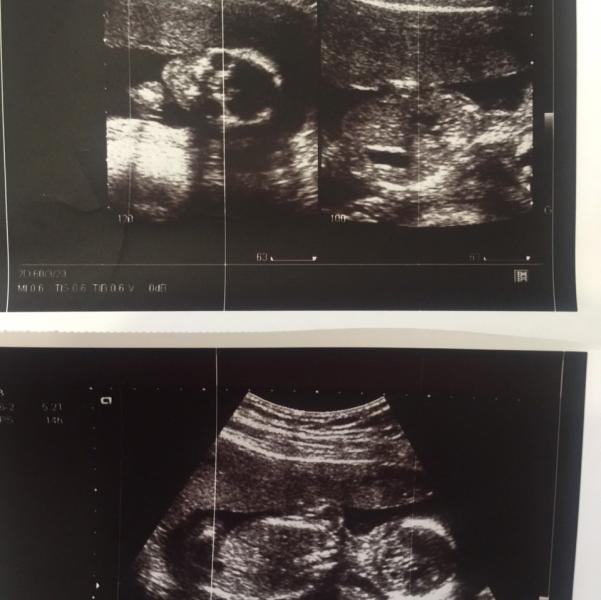

Аааааааа😍 вчера дали талон на УЗИ, а случилось бы это только 25 мая.... Но я не терпеливая козявка пригласила сегодня мужа на утреннее рандеву в Керуен😋 показали наше чудо🍭 все вокруг твердили пацан пацан.... А мы с мужем (каждый в своих мыслях)знали что там дочурка💃🏻такая сладкая обезьянка моя🙈увидела что на неё папа смотрит сразу ручками прикрылась, а потом отвернулась😋врединка моя😈чудесный врач нас смотрела, Щеголева Татьяна Борисовна, все показала рассказала, очень долго и тщательно все осмо...